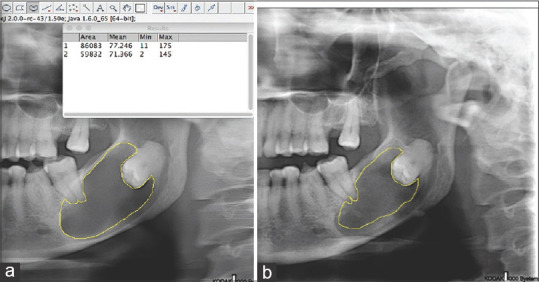

Materials and methods: Data were analysed from 40 cases, including 31 cases of odontogenic cyst and 9 cases of cyst-like tumour, treated at Chulalongkorn University's Faculty of Dentistry from 2009 to 2019. The percentage of cystic size reduction and percentage of change in radiographic density were analysed before the procedure and three months after treatment. The density and size of the odontogenic cysts were determined using Image J software version 1.43.